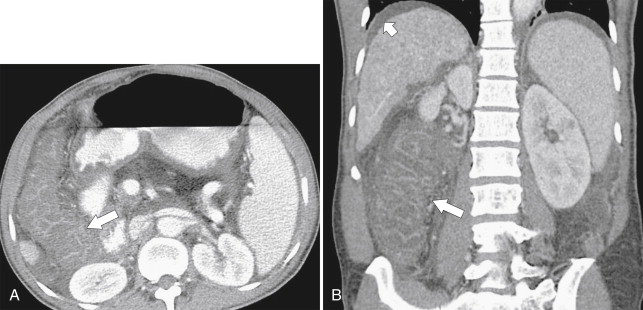

In addition to perforation from toxic megacolon, the greatest risk to patients with chronic UC is the late development of adenocarcinoma of the colon, for which they have an increased risk of 5% to 30% over the general population ( Fig. 5-18 ). The risk increases by 10% for each decade of disease. Patients with more extensive disease may therefore undergo prophylactic colectomy.

Figure 5-18, Axial ( A ) and coronal ( B ) contrast-enhanced CT in a 61-year-old woman with known ulcerative colitis and now an ascending colon adenocarcinoma ( arrows ) with associated lymphadenopathy ( small arrow ).